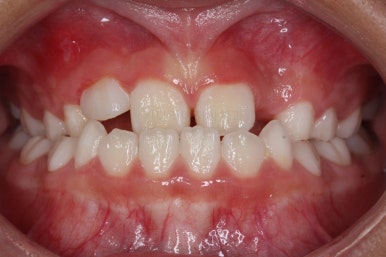

치료 시작 10개월만에 거꾸로 물리는건 개선이 되었습니다.

페이스마스크 치료는 종료했습니다.

이제 주걱턱 느낌은 없죠?

유지단계 4개월째의 모습입니다.

거꾸로 물리는 반대교합이 재발되지 않고 자리를 잘 잡고 있습니다.

위턱뼈가 넓어지다보니 처음에는 삐뚤었던 앞니도 자연스레 자리를 잡아가고 있습니다.

유지단계 11개월 경화 후의 모습입니다. 유지상태는 상당히 좋네요.

이제 유지장치도 종료하기로 하고, 앞으로는 주기적으로 아래턱이 자라나지 않는 지를 체크하게 될거에요.